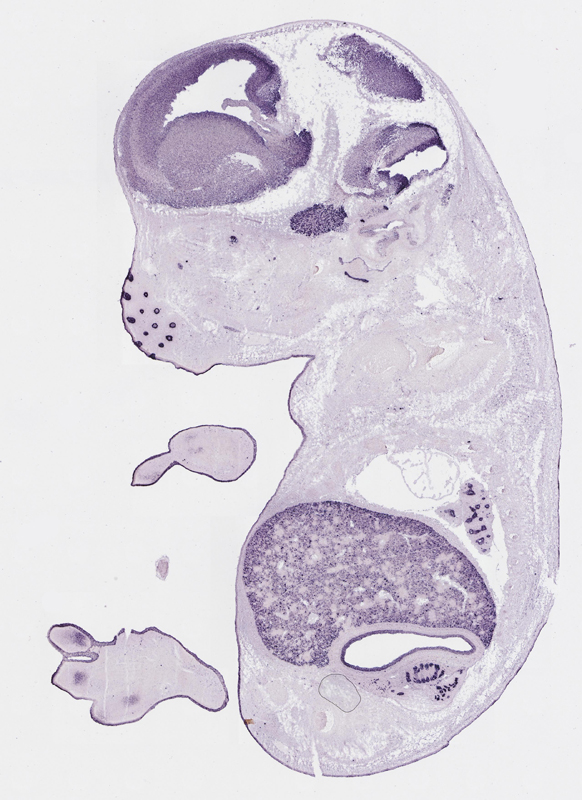

Specimen

euxassay_003287_03:

embryonic day 14.5